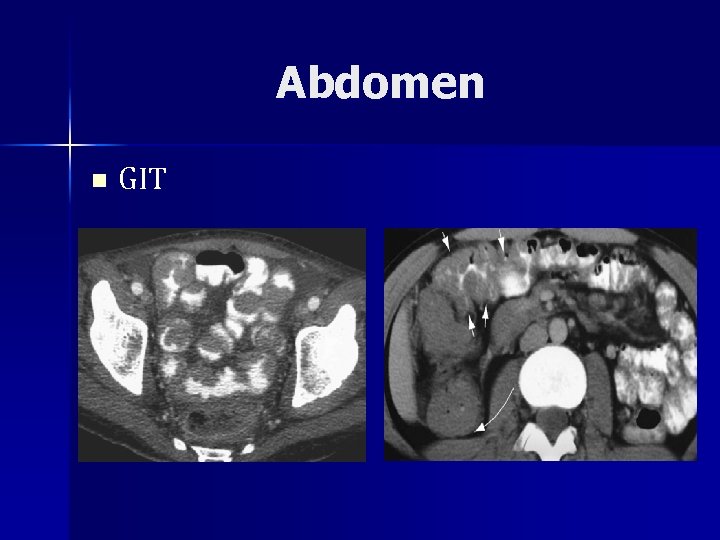

Abdomen n GIT – Most common site of 1⁰ EN NHL n 30 -45% of all n 10% adults + 30% children – 1⁰ HD of GIT rare n 2⁰ involvement common n Direct extension, multiple sites – 1⁰ lymphoma from lamina propria + submucosa

Abdomen n GIT – Frequently below the age of 10 years (BL) – Sixth decade (MALT type enteropathyassociated T-cell type) – Stomach 50%, Small bowel 35%, large bowel 15%

Abdomen n GIT – Stomach n 2– 5% of all gastric tumours n Submucosa, affecting the antrum more – Imaging n Multiple nodules, some with central ulceration, or a large, fungating lesion with or without ulceration, wall thickening, luminal narrowing, enlargement of the gastric folds (barium studies or endoscopically)

Abdomen n GIT – Imaging n Gastric wall thickening and accompanying nodal involvement, which is well shown on CT n Low grade – shallow ulceration n High grade – massive infiltration, masses

Abdomen n GIT – Small bowel n 50% of all primary tumours of the small bowel n Term ileum frequent, duodenal rare n Multifocal in 50% n Obstructive symptoms n Bowel wall thickening is well demonstrated on CT n With infiltration alternating areas of dilatation and constriction

Abdomen n GIT – Submucosal infiltration with multiple nodules or polyps of varying size result in intususception (most common cause < 6 yrs) – Barium studies typically show multiple polypoid filling defects, with or without central ulceration and irregular thickening of the valvulae.

Abdomen n GIT – Colon and rectum n Primary colonic lymphomas are usually of Burkitt or MALT subtypes n <0. 1% of all colonic neoplasms n caecum and rectum n diffuse or segmental distribution of small nodules 0. 2– 2. 0 cm in diameter n Mucosa intact n Polypoid mass uncommon, mimic ca unless term ileum involvement

Abdomen n GIT – Advanced disease, there may be marked thickening of the colonic or rectal folds resulting in focal strictures, fissures or ulcerative masses with fistula formation – Strictures longer than ca – Obstruc and rectal bleeding

Abdomen n GIT – Primary gastrointestinal lymphoma n An absence of superficial or intrathoracic lymph node enlargement n No involvement of the liver or spleen n A normal white cell count n No more than local regional lymph node enlargement

Abdomen n GIT